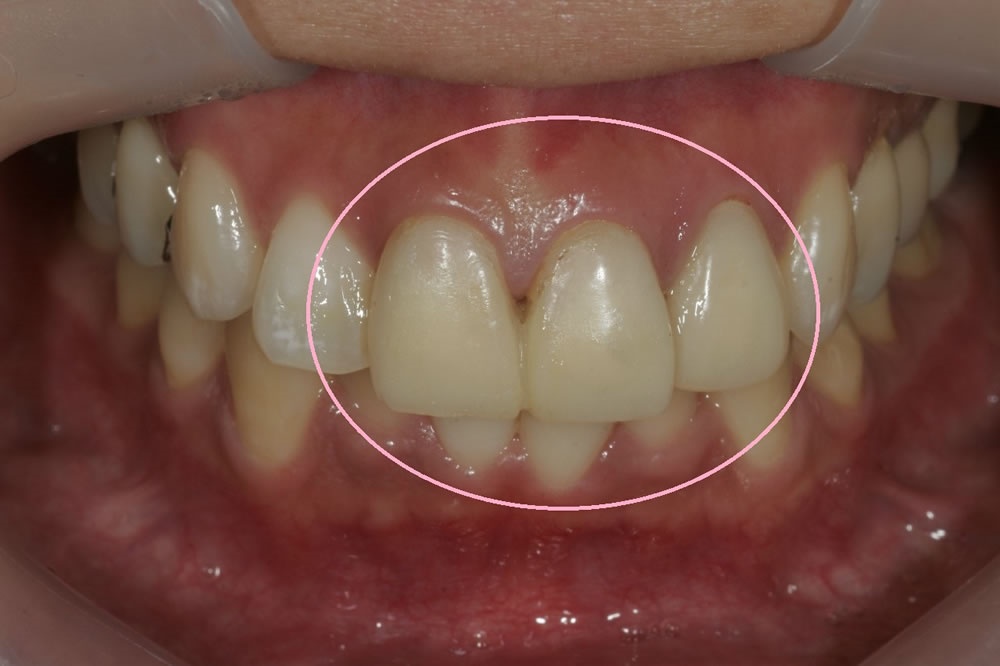

実際に当院で行った精密審美歯科治療例(前歯のオールセラミッククラウン)

こちらの患者様は転んで前歯をぶつけて他院で修復してもらったが黒ずんで来たということで来院いただいた患者様です。オールセラミック製の被せ物で修復しました。友人からもどれが人工の歯かわからないと評判とのことです。

▲神経が死んで黒ずんだ前歯、形状も不適 -

▲前歯のオールセラミッククラウン治療1年後